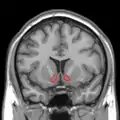

Nucleus accumbens of the mouse brain